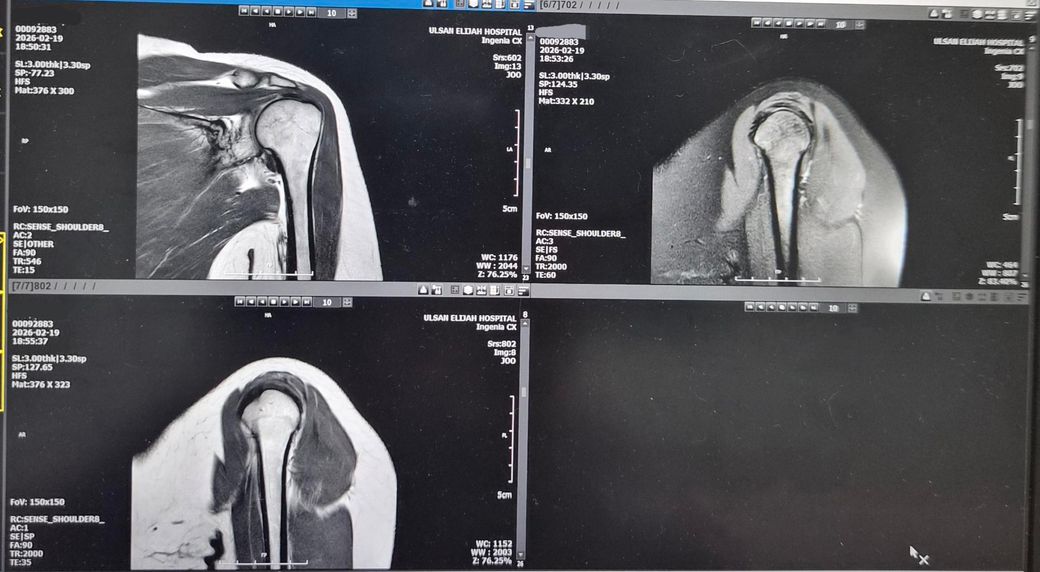

왼쪽어께가 아파서 엑스레이 찍고 MRI저녁에

찍었어요.MRI판독좀 해주세요! 의사소견으로는

골절됬다가 뼈가 붙었다고 했어요. 뼈도좀 튀어나왔죠?그리고

어께충돌증후군이 있다고 치료확인서에 적혀주셨어요. 어께안쪽이 찌릿하고 뭔가 사이에

MRI상 "어깨충돌증후군(견봉하 충돌) + 회전근개 자극/염증"이 있어 팔 들 때 걸림·찌릿함·딱딱 소리가 설명됩니다.

우선 현재로썬 전문의 소견대로 충돌증후군은 어깨 관절내의 문제가 생기면서 통증이 유발되기에 지금과 같은 증상이 나타나는것이 일반적이기에 소견이 맞을것으로 판단됩니다.